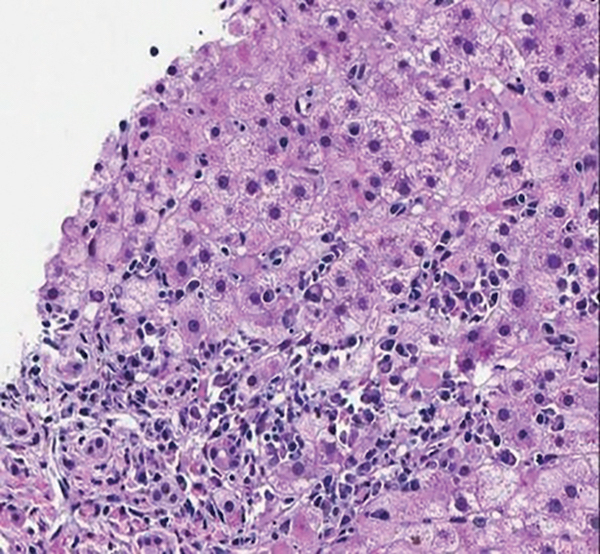

Which of the following features shown in the figure is part of the histologic criteria for autoimmune hepatitis?

A. Lymphocytes

B. Interface hepatitis

C. Ballooning degeneration

D. Non-necrotizing granuloma

The biopsy shows interface hepatitis (previously referred to as piecemeal necrosis). Interface hepatitis is a classic finding in autoimmune hepatitis and part of the diagnostic criteria when incorporating typical findings on liver biopsy. Lymphocytes on liver biopsy are not unique to autoimmune hepatitis and may be seen in other disorders, including hepatitis C, primary biliary cholangitis, and nonalcoholic fatty liver disease. Ballooning degeneration is associated with nonalcoholic fatty liver disease. Non-necrotizing granulomas are seen in sarcoidosis and primary biliary cholangitis.